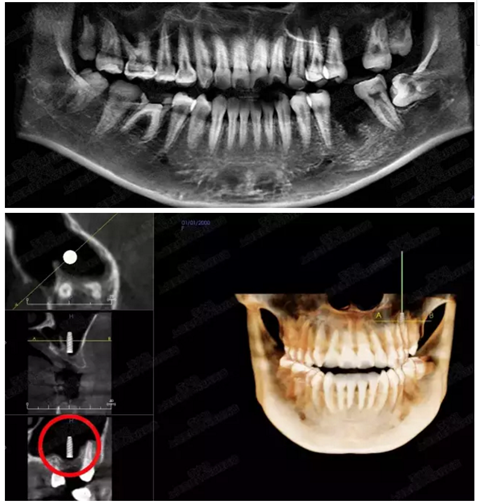

病例四

剩余骨量2mm-5mm且存在斜形竇底

007.png

提升8mm

008.png

009.png